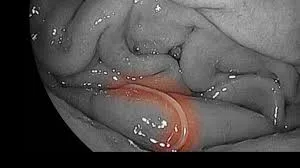

魚介類に寄生する寄生虫「アニサキス」による食中毒が全国的に急増しており、札幌市では過去10年で報告件数が約10倍に増加、年間約2万人が発症していると推計されています。テレビアナウンサーも発症し、「腹部をぎゅっとつかまれたような激痛で目が覚めた」と、その深刻な症状を語っています。アニサキスはサバ、アジ、イカ、ヒラメなど多くの魚介類に寄生する体長2~3cmの線虫で、生きたまま人間の体内に入ると胃や腸の粘膜に刺さり、激しい腹痛や嘔吐を引き起こします。症状は食後数時間~十数時間後に現れ、胃カメラによる摘出が必要となるケースもあります。予防策としては、新鮮な魚を選び、目視でアニサキスを除去すること、マイナス20℃で24時間以上の冷凍、または70℃以上の加熱が有効です。一般的な酢での処理やワサビ、醤油では死滅しないため注意が必要であり、内閣府食品安全委員会や保健所が食の安全のために注意喚起を行っています。